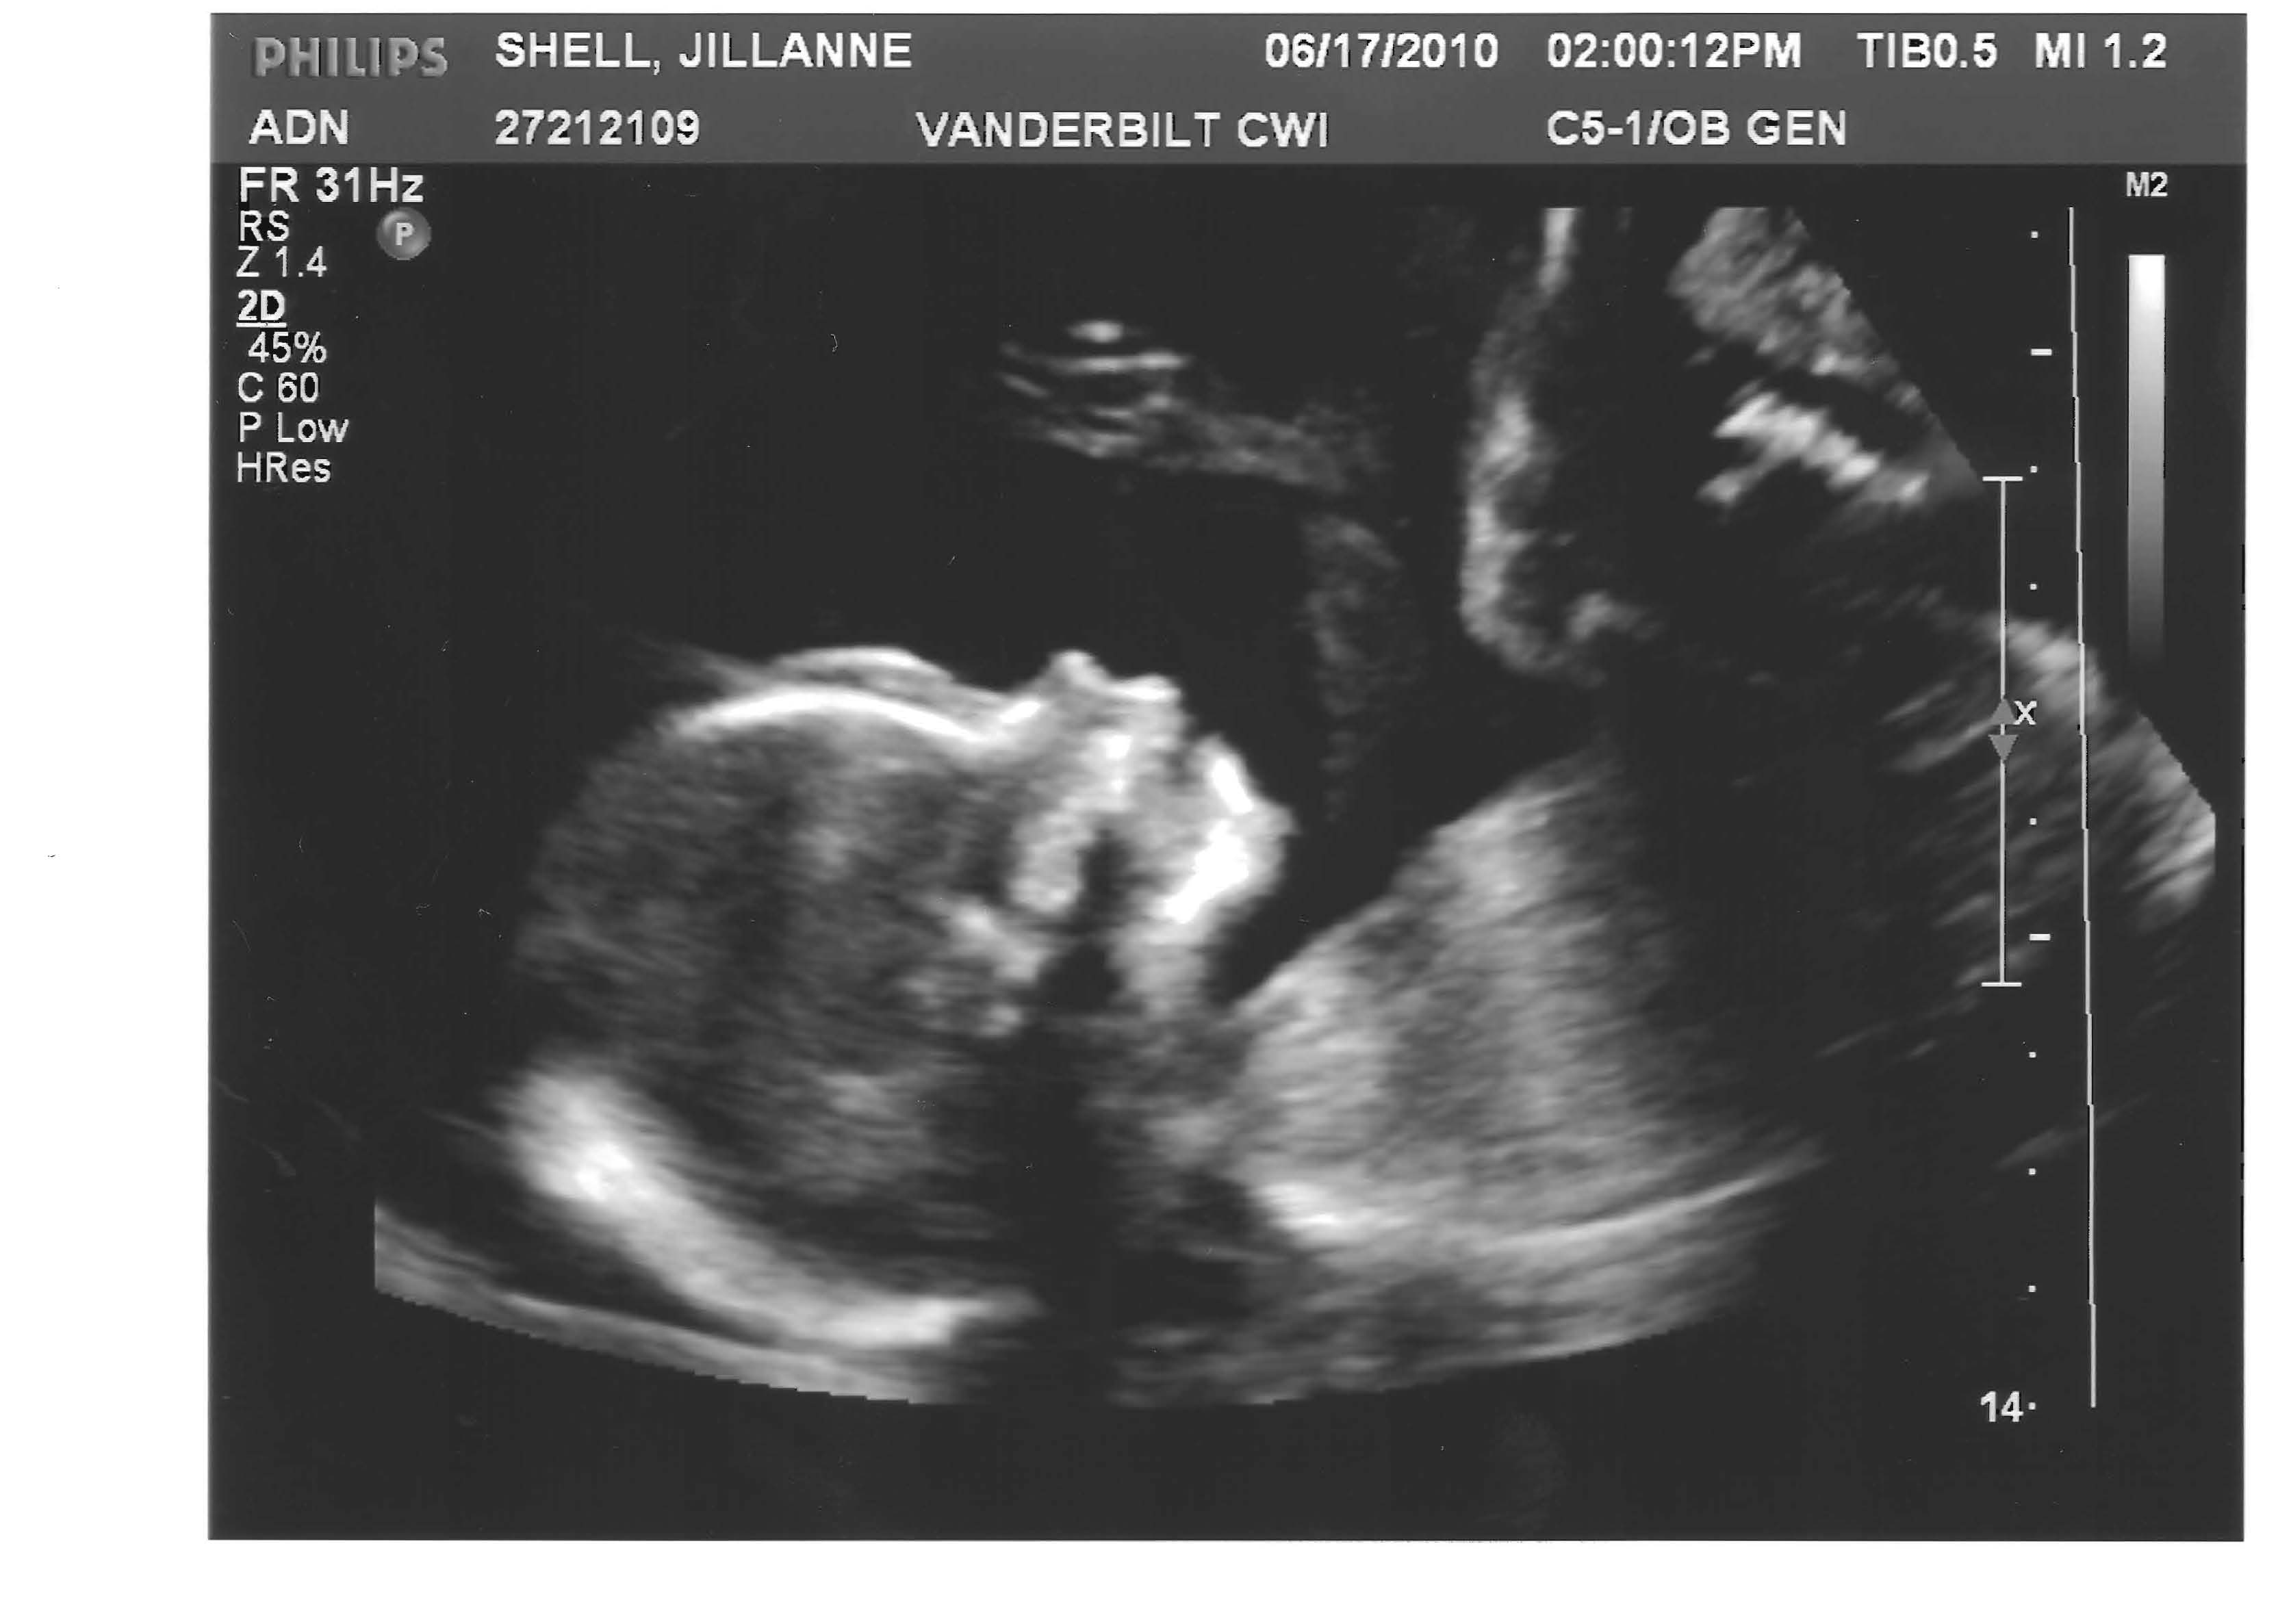

1) No epidural. We watched The Business of Being Born and wanted to do this thing as naturally as possible. We knew that statistically, a woman who is given an epidural has an increased chance of needing a C-section. So my wife decided (on her own) that she would not get an epidural unless it become absolutely necessarily.

After enduring 17 and a half hours of labor naturally, we were told that if my wife didn’t get an epidural, she would definitely have to have a C-section because she wouldn’t have enough strength to deliver him.

Five hours later, our son was born. In case you’re keeping up with the math, it was a 22 and half hour labor, only five of those hours being drug-induced. Just for the record, I could never have done that! That’s why I was born a man.